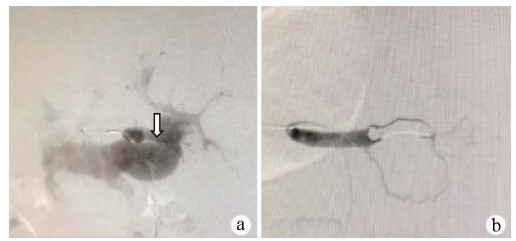

A case of splenic arteriovenous fistula with abdominal pain and gastrointestinal bleeding as the first symptoms

Yuanyuan CAI, Zhongwen WU, Juan LU

2021, 37(5): 1186-1188. DOI: 10.3969/j.issn.1001-5256.2021.05.043

Abstract(1011) HTML (291) PDF (2876KB)(49)

Abstract: